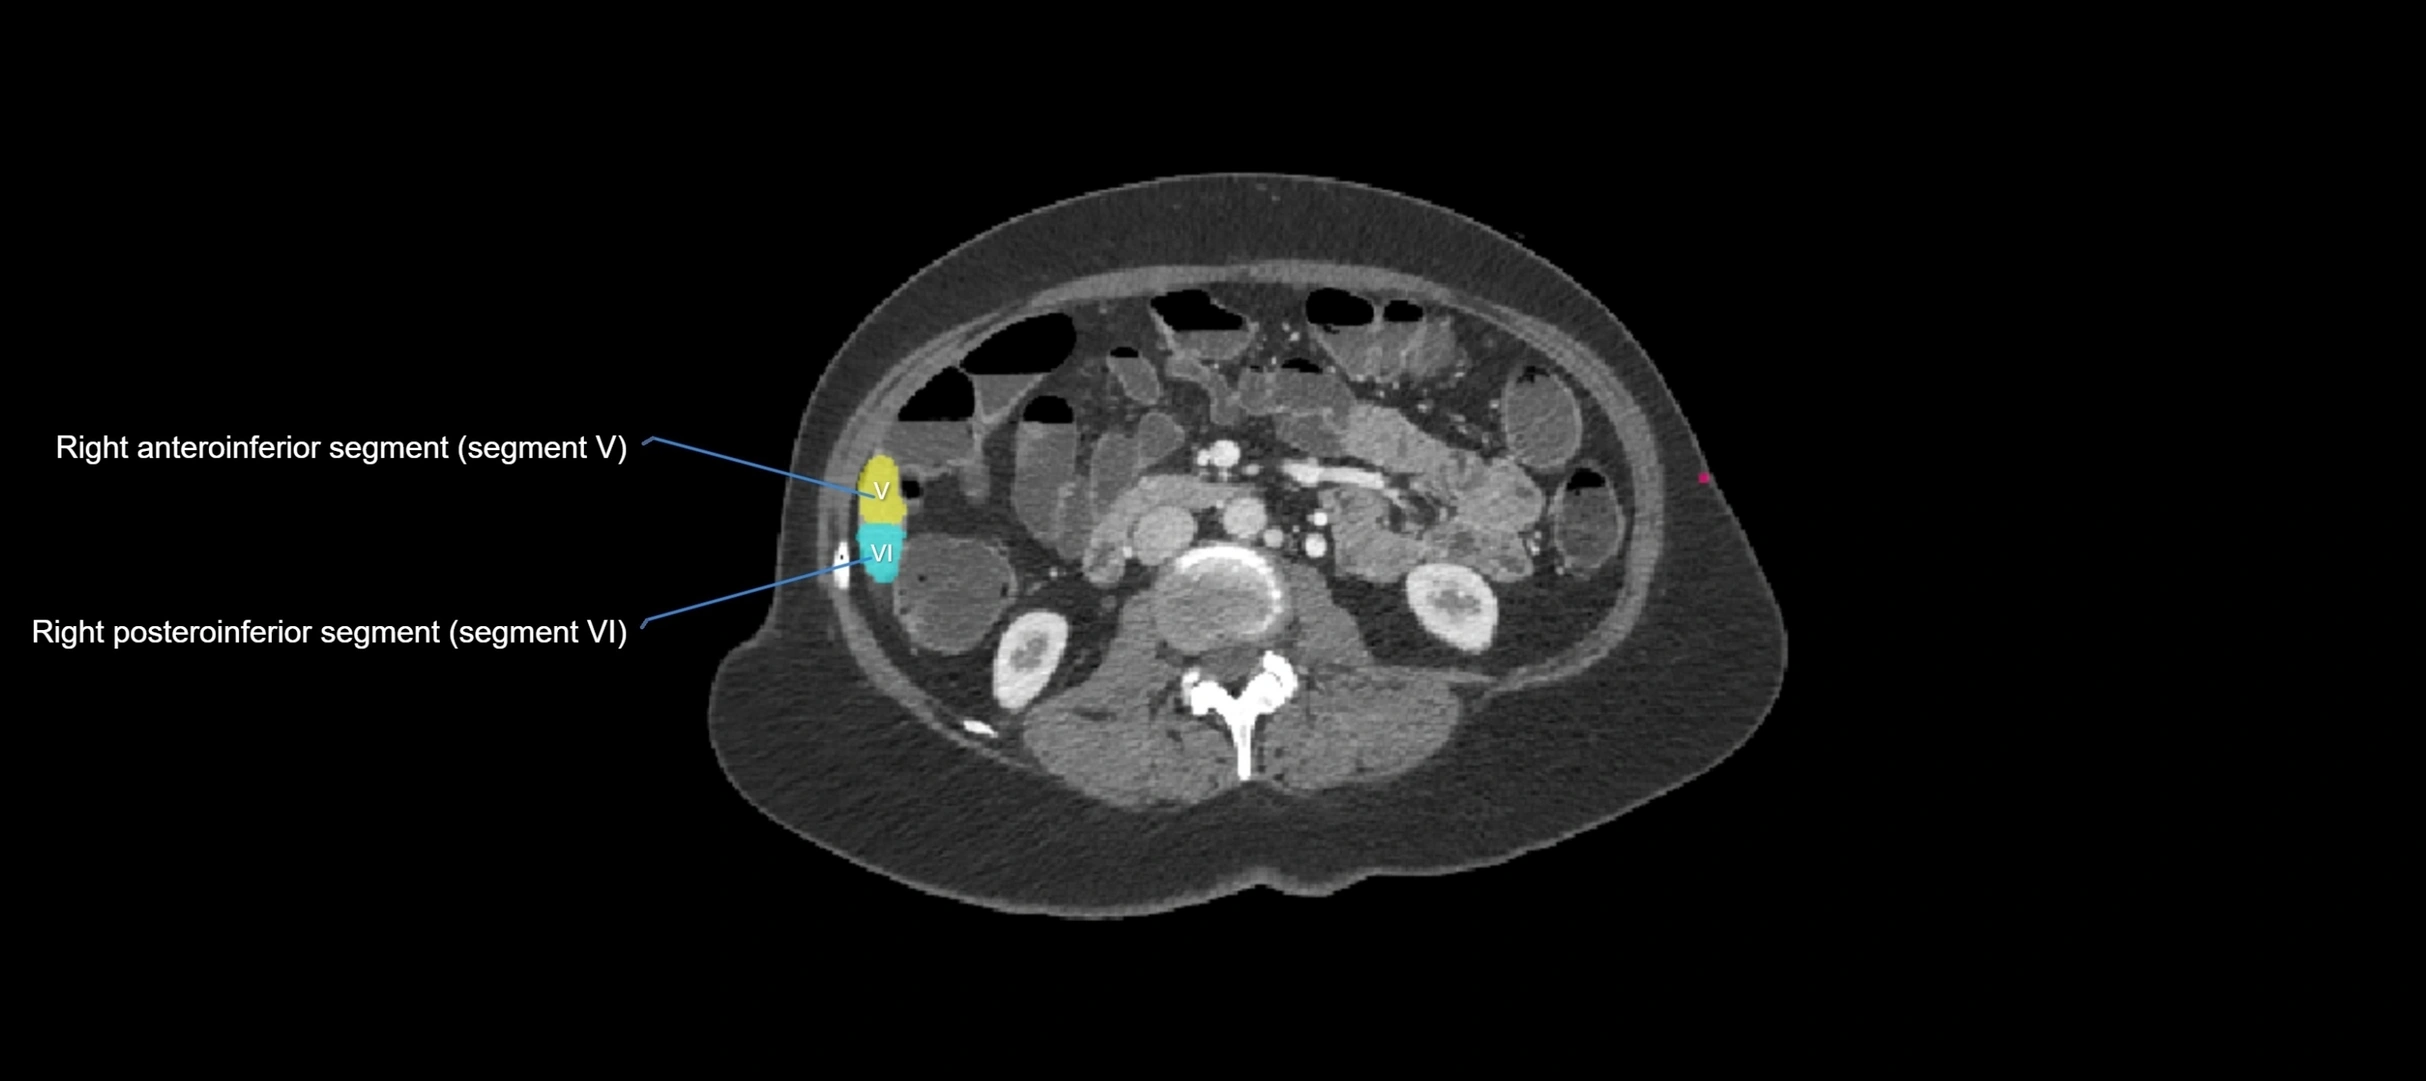

CT Appearance

CT Pre-Contrast:

• Caudate lobe appears as a soft-tissue density, isodense to the rest of the liver

CT Post-Contrast:

• Homogeneous enhancement in the portal venous phase, similar to rest of liver

• Independent venous drainage into the IVC may be visualized

• Lesions follow characteristic CT enhancement patterns (HCC: arterial hyperenhancement with washout; hemangiomas: peripheral nodular enhancement with centripetal fill-in)

CT Image

image